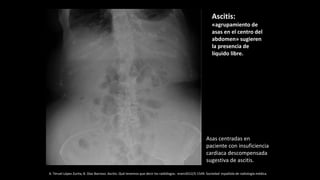

Asas centradas en

paciente con insuficiencia

cardiaca descompensada

sugestiva de ascitis.

Ascitis:

«agrupamiento de

asas en el centro del

abdomen» sugieren

la presencia de

líquido libre.